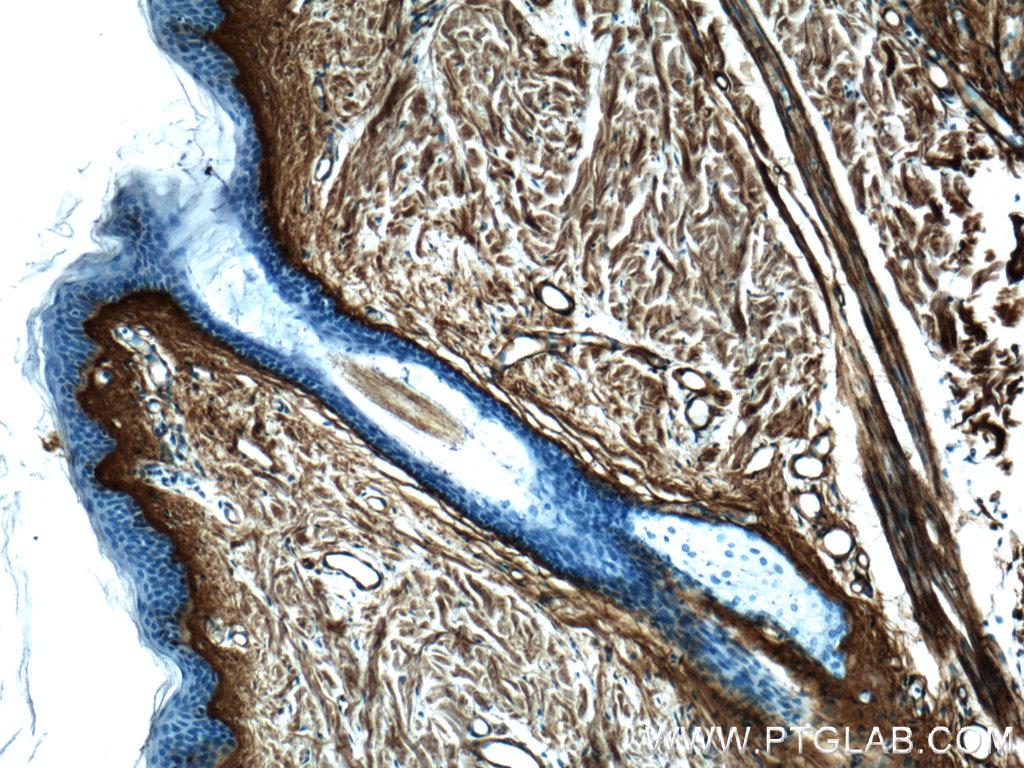

| Positive IHC detected in | human hepatocirrhosis tissue, human pancreas cancer tissue, mouse liver tissue, mouse kidney tissue, human colon tissue, human skin cancer tissue, mouse heart tissue, mouse colon tissue, human skin tissue, human malignant melanoma tissue Note: suggested antigen retrieval with TE buffer pH 9.0; (*) Alternatively, antigen retrieval may be performed with citrate buffer pH 6.0 |

22734-1-AP targets Collagen Type III (N-terminal) in WB, IHC, IF-P, IF-Fro, IP, CoIP, ELISA applications and shows reactivity with human, mouse, rat samples.

Type III collagen is a fibrillar forming collagen comprising three α1(III) chains and is expressed in early embryos and throughout embryogenesis (PMID: 9050868). In the adult, type III collagen is a major component of the extracellular matrix in a variety of internal organs and skin. It occurs in most soft connective tissues along with type I collagen (PMID: 2445760). COL3A1 gene encodes type III procollagen. Mutations in this gene are associated with Ehlers-Danlos syndrome types IV, and with aortic and arterial aneurysms (PMID: 10706896; 2243125; 18389341). This antibody raised against 24-152 aa of prepro α1 (III) chain of human type III procollagen detects type III procollagen at 140-180 kDa and also in some lysates reveals a 70-kDa band which has been reported and may represent a cleaved form of type III procollagen (PMID: 17424834; 19648160; 22802960).